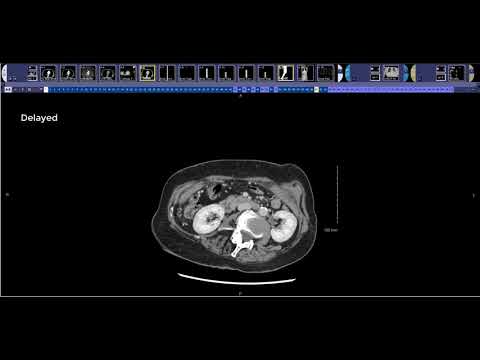

How to read a Renal Mass CT